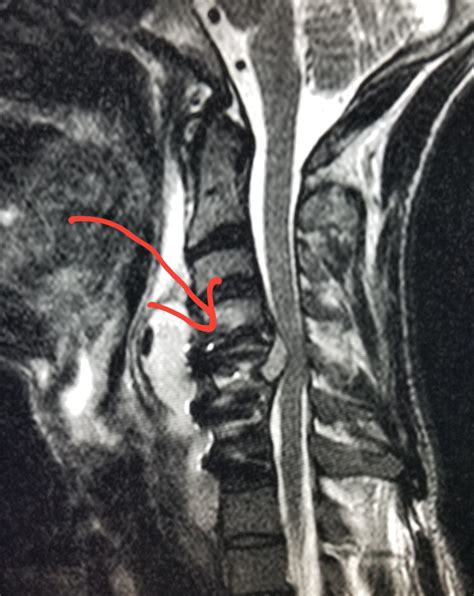

Epidural Injections | Nona Medical Arts - Injections for Neck and Back Pain